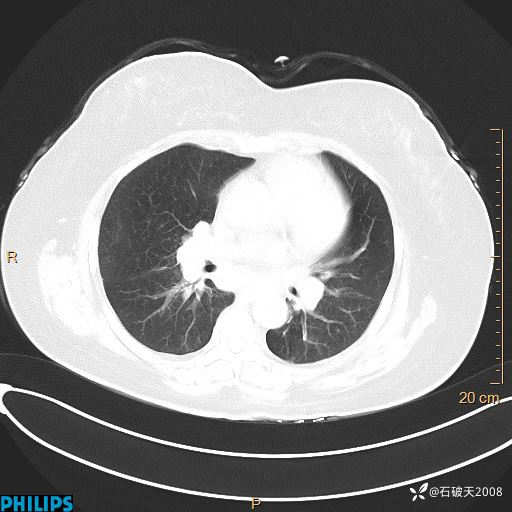

肺结节病?纵膈型肺癌?淋巴瘤?有点意思,欢迎围观

女 52岁 主 诉:咳嗽10余天,咳痰2天。

现病史:10余天前无明显诱因出现咳嗽,呈阵发性干咳,伴咽喉部发痒,无咽痛,无咳痰,无鼻塞、流涕、打喷嚏,无发热、畏寒、寒颤,无头痛、头晕,无胸闷、胸痛,无反酸、烧心,无腹痛、腹泻,无尿频、尿急,无皮疹等,在当地诊所求治,给予口服药物治疗(具体不详),病情无好转。遂在当地社区卫生服务中心开具口服药物治疗(具体不详),疗效欠佳。2天前出现咳痰,在我院门诊求治,行胸部CT提示肺部感染,建议住院,患者要求口服药物治疗,目前仍咳嗽、咳白色粘痰,白天量多,夜间自觉喉部喘鸣音,遂再次来院就诊,以“肺部感染”为诊断收入院。发病以来,神志清,精神可,饮食可,夜间睡眠差,大小便正常,近期体重无明显变化。

肺窗